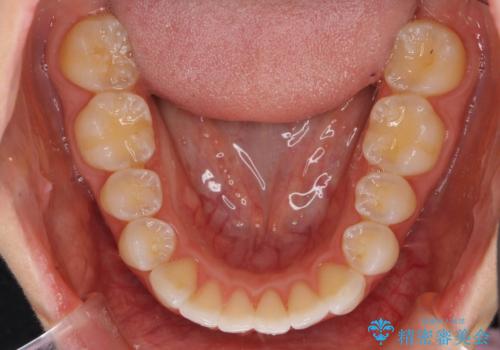

前歯のがたつき インビザラインで

- 前歯のがたつきを治したいとのことでした。歯を抜かずにできる範囲で引っ込めたいとのことでした。

歯列の側方拡大(横に広げる)と、エナメル質の削合で並べました。

歯を抜いているわけではないので、口元はそこまで変化はありませんが、前に出すことなくデコボコは取れたと思います。